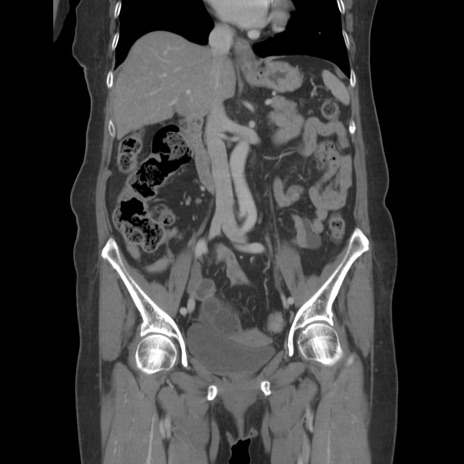

症例19(冠状断像)

【症例】80歳代女性

【主訴】下腹部痛

【現病歴】約8時間前より下腹部痛の出現あり、救急外来受診。

【既往歴】両側付属器切除

【身体所見】意識清明、下腹部正中に手術痕あり、その部位に一致して圧痛と反跳痛あり。腸蠕動音は亢進。

【データ】WBC 9300、CRP 0.15